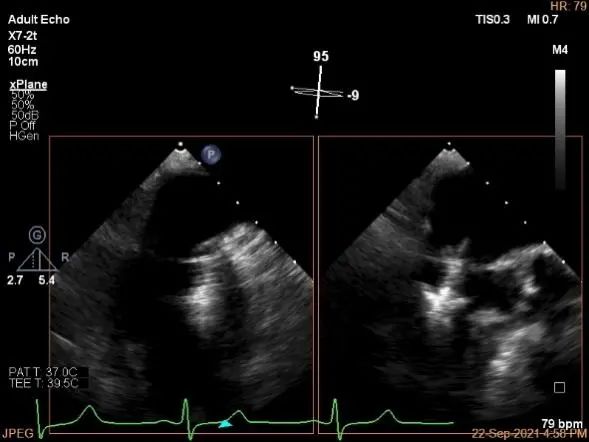

未见明确残余分流

三维评估两个夹子位置

3D-color再次确定未见残余分流

评估瓣口条件,平均跨瓣压差:4mmHg

肺静脉血流频谱恢复正常